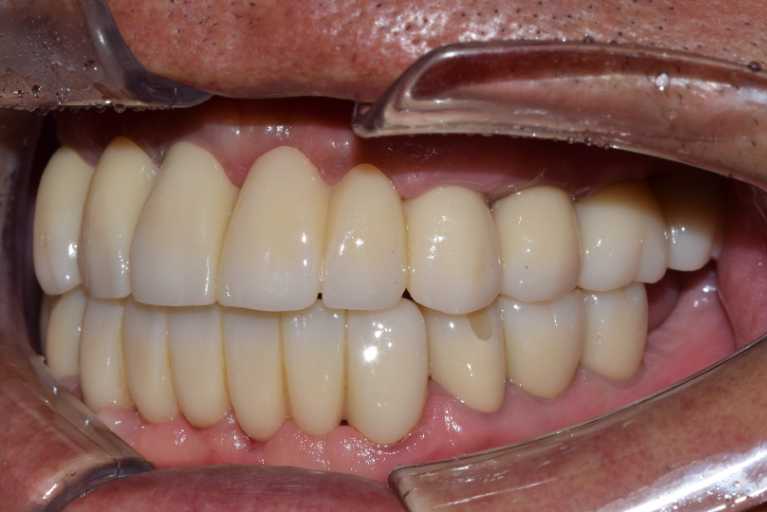

고정형 무치악 임플란트 전후 사례

무치악 임플란트 전후 실제 사례 #1, #2

이미지 위에 가운데 동그라미를 클릭한 상태에서 왼쪽 또는 오른쪽으로 드래그해보세요! 드래그할 때마다 환자의 전후 변화를 확인하실 수 있습니다.

#무치악 임플란트 환자 사례 : 임플란트로 찾은 새로운 미소